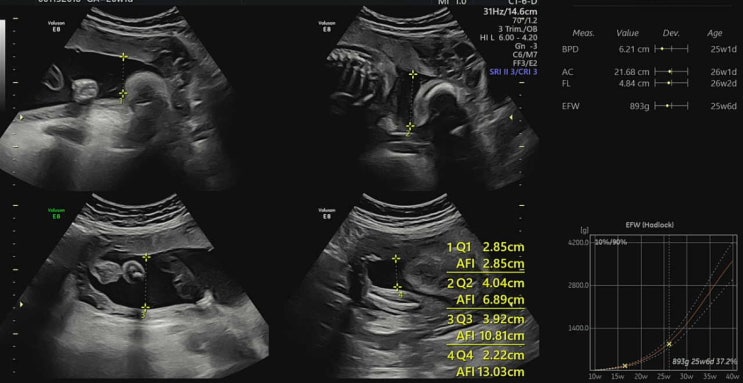

D-93 , 26주 5일

하동이의 두번째 기록 시간이 너무 빨리 지나가는데 하루하루가 아쉬운 지경 그사이 정밀 초음파도 봤고 임...